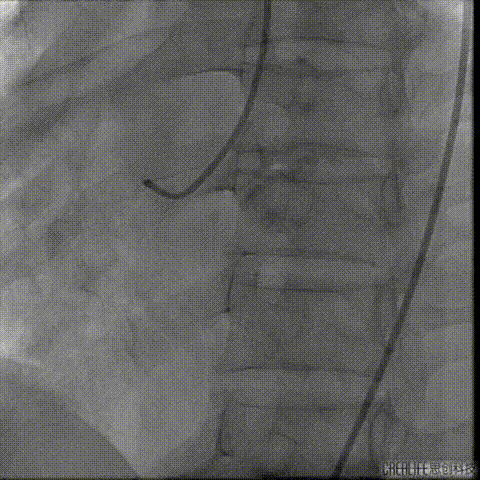

冠脉造影

瓣上造影

猪尾导管位于右窦

严重反流导致造影效果欠佳

左冠显示不清 结构显示不清